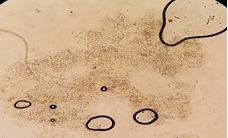

• Nấm da :thấy sợi nấm trong suốt, có vách ngăn, có thể thấy bào tử đốt.

Hình 3: Nấm da